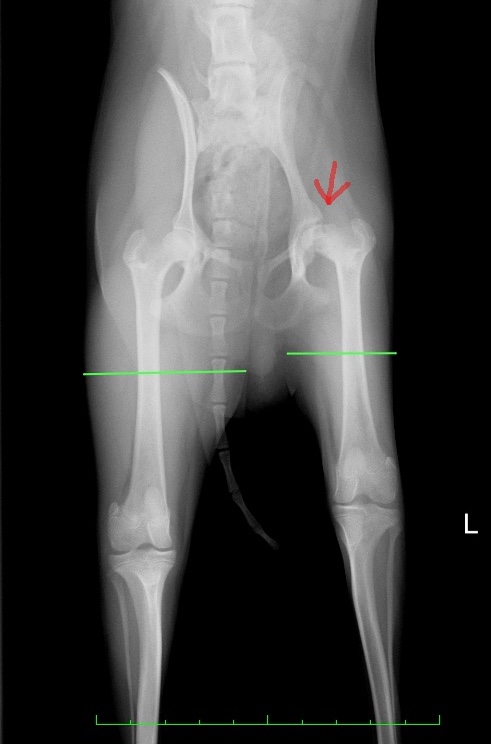

術前の股関節のX線写真では、正常な右の大腿骨頭は綺麗な球形ですが、左は球形が崩れ、X線の透過性も変化しまだらに見えています。(赤矢印)

またモモの筋肉の太さが明らかに違います。(緑線)

罹患肢の左が細いのは、廃用性萎縮といい、痛みによって長期間うまく体重をかけられなかった結果として筋肉が痩せてしまったことによります。

術前X線